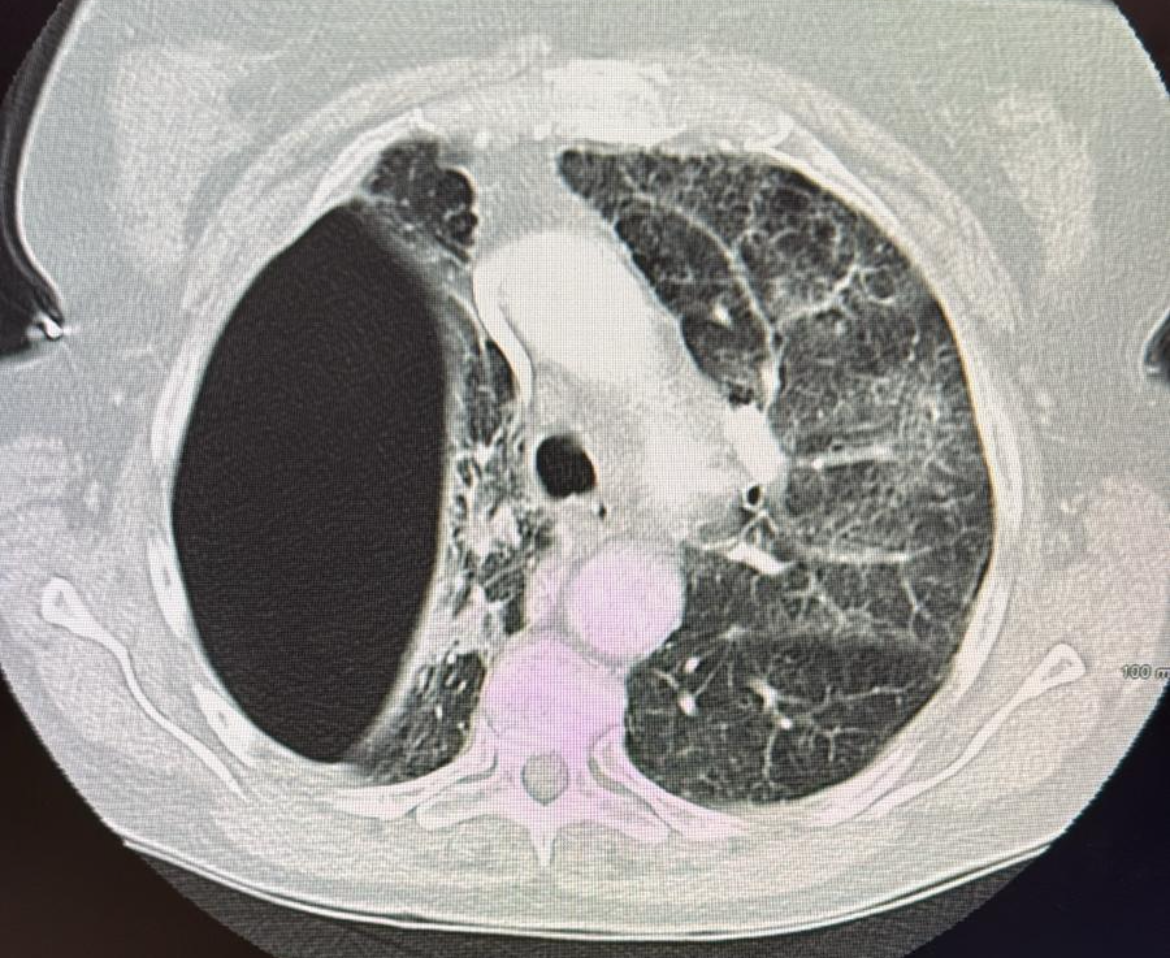

Strokes and Management

What I think you should known regarding the types of strokes and management

Strokes and how to manage them!